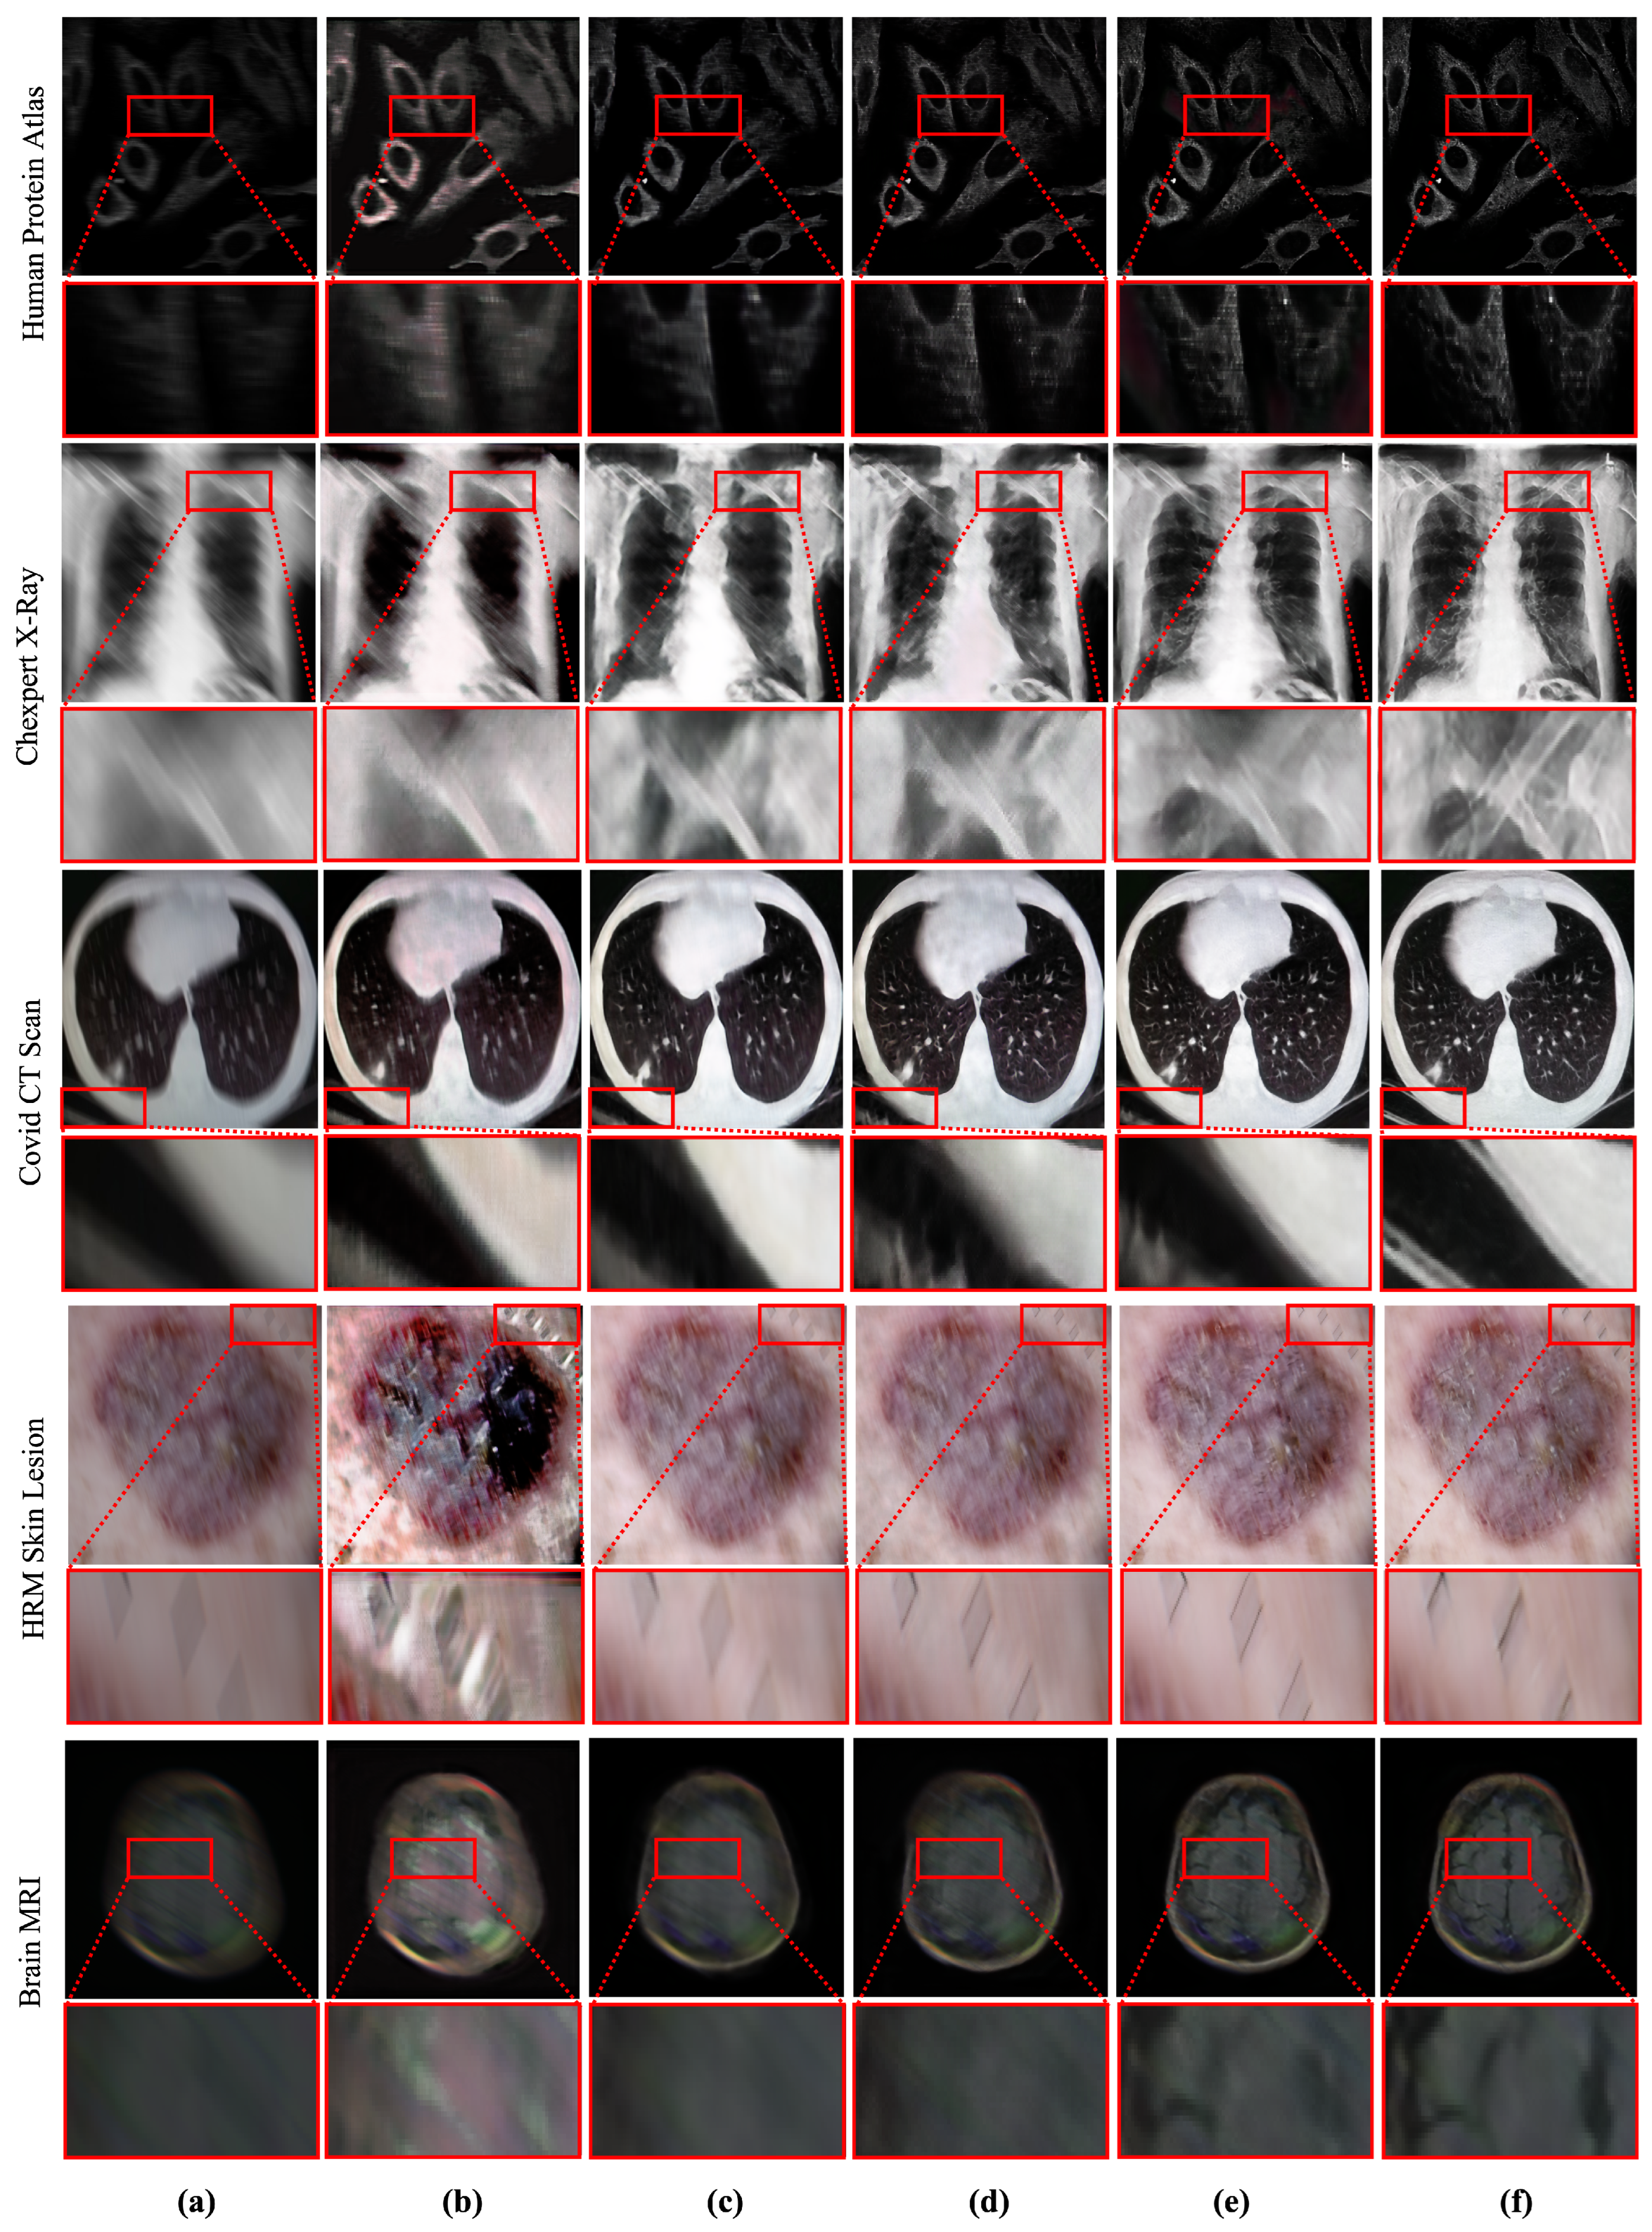

Oppositely, deep learning-based image deblurring techniques have evolved significantly in the past decade [10]. These methods have illustrated significant improvement in removing deblurs in non-medical images. Notably, the deep deblurring methods outperform traditional counterparts by a considerable margin in diverse data samples [10]. To examine the existing deep deblurring techniques for MID, we trained and tested these methods on medical images collected from multiple image modalities, as shown in Figure 1. It has been found that the existing state-of-the-art (SOTA) deep deblurring and MID methods fail to recover texture and salient information from blurry medical images. Moreover, they are prone to produce visually disturbing artifacts while removing blur from the given image.

Figure 1.

Performance of existing medical image deblurring methods in removing blind motion blur. The existing deblurring methods immensely failed in removing blur from medical images. (a) Blurry input. (b) Result obtained by TEMImageNet [9]. (c) Result obtained by ZhaoNet [11]. (d) Result obtained by Deep Deblur [12]. (e) Result obtained by SRN Deblur [13]. (f) Proposed Method.

It is worth noting that medical images are typically captured with different image acquisition mechanisms and comprise more salient features than non-medical images. However, removing blur from medical images has a significant impact. It can substantially accelerate the performance of medical image analysis tasks. Despite a wide range of applications and real-world impacts, the performance of existing MID methods is inadequate. They fail to address the large-kernel blind blurs in medical images, as shown in Figure 1. The limitation of existing methods motivated this study to incorporate a robust learning-based MID solution, which can handle the large kernel blurs without explicitly considering image modality.